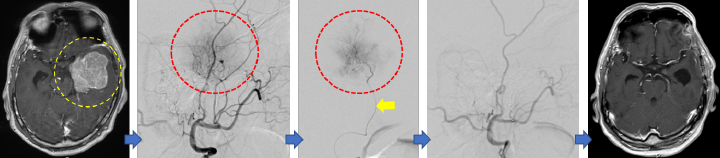

脳腫瘍に対する脳血管内治療

髄膜腫など一部の脳腫瘍に対し、手術中の出血を少量にして手術を安全に行えるようにするため、手術前に腫瘍の栄養血管を脳血管内治療により閉塞します。

MRIで、大きな髄膜種を認めます(黄点線内)。脳血管撮影を行うと、強い腫瘍陰影(赤点線内、腫瘍を栄養する血管)を認めます。腫瘍の栄養血管までマイクロカテーテルをすすめ(黄矢印)、栄養血管を閉塞します。これにより手術中の出血を少量にし、安全に手術が可能です。腫瘍は全摘出されました。